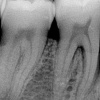

Luukadu agressiivse parodontiidiga patsiendil